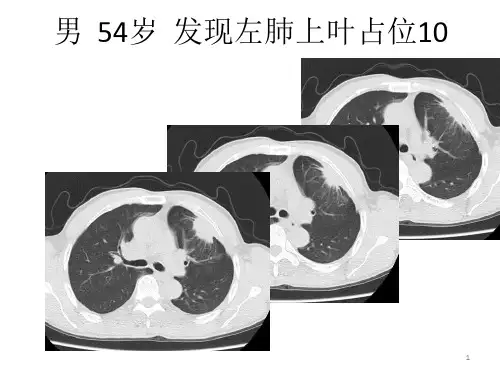

原发性肺癌

(一)临床与病理

1.起源 支气管的上皮,腺体, 细支

气管及肺泡上皮

2.组织学分型:鳞癌,腺癌, 末分化细胞癌,细支气管肺泡癌,

3.放射学分型

(1)中心型:发生于主支气管、叶

支气管

(2)周围型:发生于段支气管及段以 下至细支气管以上

(3)细支气管肺泡癌:发生于细支气 管、肺泡上皮

4.生长方式 (1)中心型:结节型,浸润型,结节浸润型

(2)周围型:实体性生长:癌细胞充满肺泡——沿 肺泡孔向周围生长——实性肿块

浸润性生长: 弥漫型:癌细胞——肺泡壁呈覆 壁生长, 肺泡充气,肺泡间隔无破坏 局灶性:病灶中心纤维结缔组织增生且 伴有炭末沉积——邻近支气管 牵拉向瘤体中心